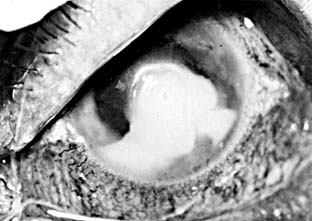

Pseudomonas corneal ulcer begins as a gray or yellow infiltrate at the site of a break in the corneal epithelium (Figure 6-2). Severe pain usually accompanies it. The lesion tends to spread rapidly in all directions because of the proteolytic enzymes produced by the organisms. Although superficial at first, the ulcer may affect the entire cornea. There is often a large hypopyon that tends to increase in size as the ulcer progresses. The infiltrate and exudate may have a bluish-green color. This is due to a pigment produced by the organism and is pathognomonic of P aeruginosa infection.

Figure 6-2

Figure 6-2: Pseudomonsa ulcer related to 24-hour contact lens wear.